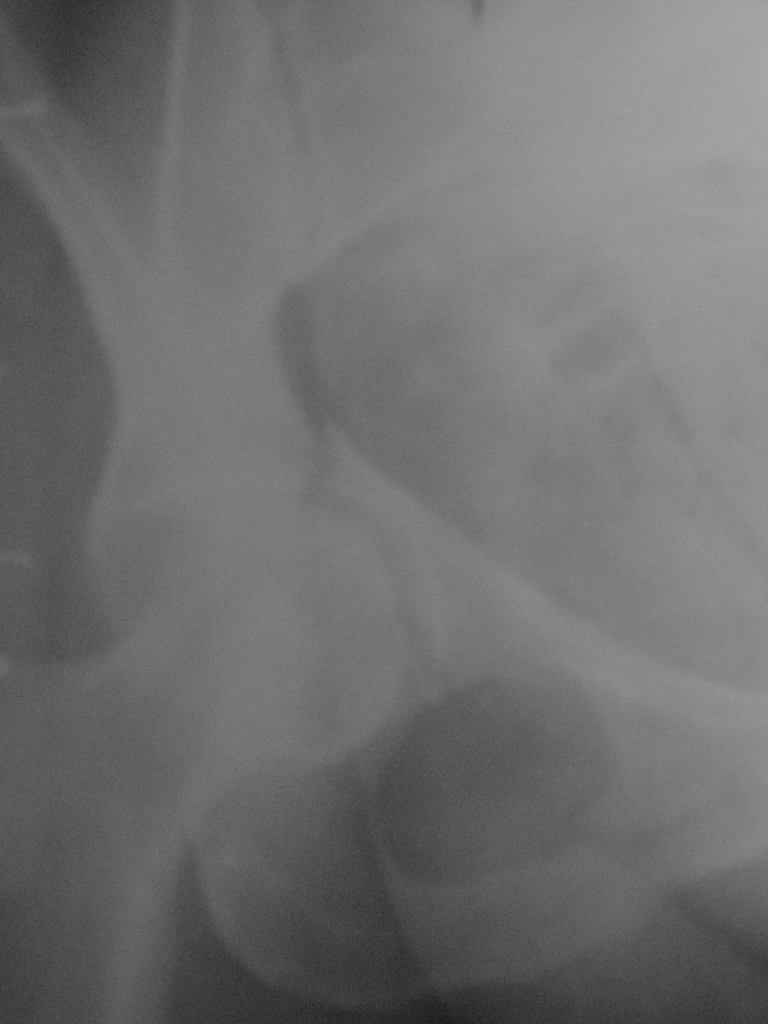

Женщина,58 лет, после ДТП 6 суток. Первично повреждение расценено как переломы ветвей

лонной кости.

сломался. Прилагаю стандартные снимки вертлужки. У меня следующие вопросы к коллегам: 1.

Правильно ли рассценивать это повреждение как Т-образный перелом вертлужнй впадины? 2.

Можно ли добиться анатомической репозиции поверхности вертлужной впадины скелетным

вытяжением в данном случае, если нет, что будет этому препятствовать? 3. Если смещение

останется таким как сейчас, через какое время появится необходимость эндопротезирования

(по вашему опыту)? Спасибо.